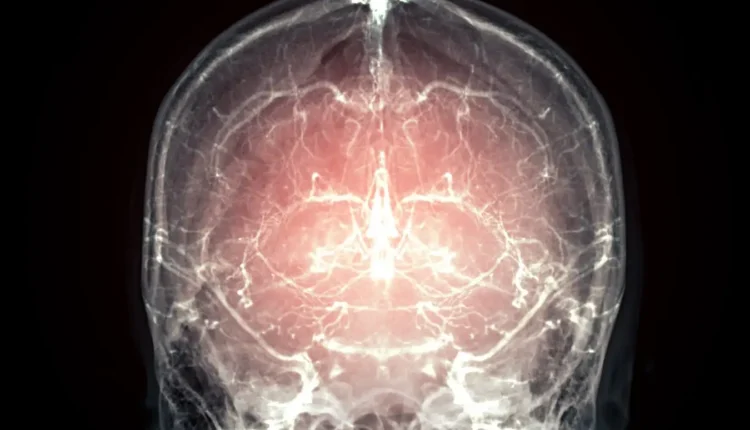

Σημαντικό βήμα προς την ανάνηψη μετά τον θάνατο: Διατηρήθηκε εγκεφάλου θηλαστικού

Ένας ολόκληρος εγκέφαλος θηλαστικού έχει διατηρηθεί με επιτυχία χρησιμοποιώντας μια τεχνική που θα προσφέρεται πλέον σε ασθενείς με τελική ασθένεια. Στόχος είναι η διατήρηση όλων των νευρωνικών πληροφοριών που θεωρούνται απαραίτητες για την αναδημιουργία του μυαλού του ατόμου στο οποίο ανήκε, κάποια στιγμή στο μέλλον.